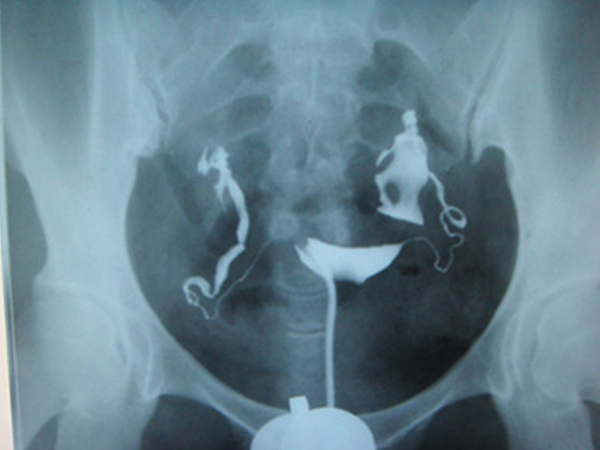

在无菌操作下抽出造影剂7-10毫升开始注入,在透视下边注入边观察,当子宫和输卵管全部充盈时就开始拍片。如果注射的是碘水剂,可以间隔15分钟左右连续拍两片;如果注射的是碘油剂,则在24小时后再拍一次盆腔片。